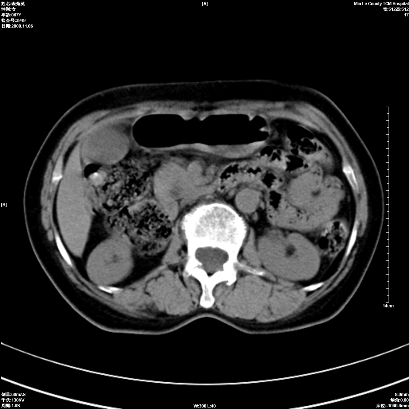

以下是引用卜一在2008-11-6 15:58:00的发言:[br]胰头略增大,胆总管扩张,末端渐行性狭窄。多考虑:胰头癌!建议增强!

以下是引用huangyinshan在2008-11-6 16:32:00的发言:[br]胰头略增大,胆总管扩张,末端渐行性狭窄。多考虑:胰头癌!建议增强!